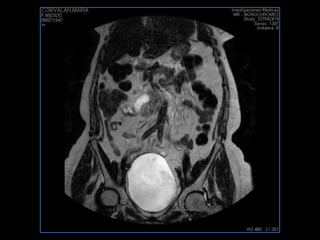

PROTOCOLO pelvis SAG T2, Y FAT SAT (FINOS) AXIAL T1  AX FAT SAT CON   GADOLINIO :  AX T1 Y COR T1 SAT: NO  FASE: RL THK: 3MM  COIL:  GAP: (FACTOR 1.4) 1MM FOV: 40 CM NEX:2 SINCRONIZACION RESPIRATORIA EN 3 O 4 CICLOS ALE

resonancia de abdomen